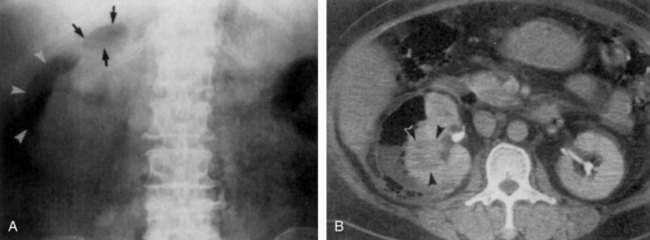

The diagnosis is established radiographically. Tissue gas that is distributed in the parenchyma may appear on abdominal radiographs as mottled gas shadows over the involved kidney (Fig. 10–22). This finding is often mistaken for bowel gas. A crescentic collection of gas over the upper pole of the kidney is more distinctive. As the infection progresses, gas extends to the perinephric space and retroperitoneum. This distribution of gas should not be confused with cases of emphysematous pyelitis in which air is in the collecting system of the kidney. Emphysematous pyelitis is secondary to a gas-forming bacterial UTI, often occurs in nondiabetic patients, is less serious, and usually responds to antimicrobial therapy.

Figure 10–22 Emphysematous pyelonephritis; plain film. Extensive perinephric (long arrows) and intraparenchymal (short arrows) gas secondary to acute bacterial pyelonephritis.

(From Schaeffer AJ. Urinary tract infections. In: Gillenwater JY et al, editors. Adult and pediatric urology. Philadelphia: Lippincott William & Wilkins; 2002. p. 211–72.)

Ultrasonography usually demonstrates strong focal echoes suggesting the presence of intraparenchymal gas (Brenbridge et al, 1979; Conrad et al, 1979). CT is the imaging procedure of choice in defining the extent of the emphysematous process and guiding management (Figs. 10-23 and 10-24). An absence of fluid in CT images or the presence of streaky or mottled gas with or without bubbly and loculated gas appears to be associated with rapid destruction of renal parenchyma and a 50% to 60% mortality rate (Wan et al, 1996; Best et al, 1999). The presence of renal or perirenal fluid, the presence of bubbly or loculated gas or gas in the collecting system, and the absence of streaky or mottled gas patterns is associated with a less than 20% mortality rate. Obstruction is demonstrated in approximately 25% of the cases. A nuclear renal scan should be performed to assess the degree of renal function impairment in the involved kidney and the status of the contralateral kidney.